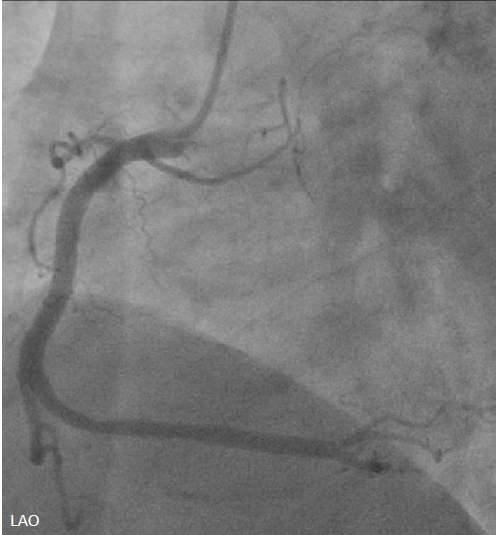

Emergent cardiac catheterization revealed patent left main coronary artery with total occlusion of the proximal left anterior descending artery (LAD). The left circumflex and right coronary arteries were patent. The culprit lesion was the proximal LAD.

The left coronary artery was engaged with an XB 3.5¡¿6 Fr guide catheter. Using a Fielder FC guidewire with a Fine-Cross microcatheter, the distal LAD was successfully accessed. Pre-dilation with a 1.5¡¿20 mm balloon demonstrated residual stenosis with poor flow. Further dilation with a 2.0¡¿15 mm balloon improved flow. Intravascular ultrasound (IVUS) revealed intramural hematoma (IMH) in the proximal-to-mid LAD. A drug-eluting stent (BMX6 2.75¡¿33 mm) was deployed from the proximal LAD (distal to the first diagonal branch) to the mid LAD, followed by proximal post-stent dilation with a 4.0¡¿12 mm non-compliant balloon at 4-16 atmospheres. Post-deployment IVUS confirmed adequate stent expansion without malapposition. Final coronary angiography demonstrated TIMI grade 3 flow.